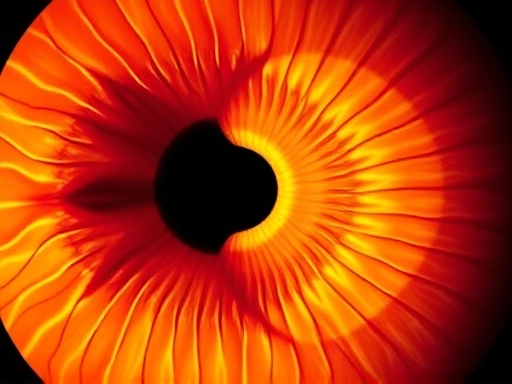

이 검사는 플라시도 링(Placido Rings)이라는 원형 고리 패턴을 각막에 비추고, 이 패턴이 각막 표면에서 반사되는 형태를 컴퓨터로 분석하여 각막의 곡률과 높낮이를 측정하는 원리를 이용합니다. 색깔로 표시된 지형도 이미지로 결과를 보여주는데, 따뜻한 색상(빨강, 주황)은 각막이 가파른(steep) 부분을, 차가운 색상(파랑, 초록)은 편평한(flat) 부분을 나타냅니다. 이를 통해 각막 전체의 지형도를 한눈에 파악할 수 있게 됩니다.

각막 지형도 검사 결과는 다양한 색상과 패턴으로 표현된 지도를 통해 환자의 각막 상태를 시각적으로 보여줍니다. 이 지도는 크게 두 가지 주요 정보를 제공합니다. 첫째, 각막의 굴곡도를 나타내는 곡률 지도(Curvature Map)와 둘째, 각막 표면의 실제 높낮이를 보여주는 고도 지도(Elevation Map)입니다. 이 두 가지 지도를 종합적으로 분석하여 각막의 건강 상태와 수술 가능 여부를 판단하게 됩니다.

곡률 지도에서는 각막의 편평한 정도와 가파른 정도를 색상으로 구분합니다. 일반적으로 따뜻한 색상(빨강, 주황)은 각막이 더 가파르거나 굴절력이 강한 부분을, 차가운 색상(파랑, 초록)은 각막이 더 편평하거나 굴절력이 약한 부분을 나타냅니다. 정상적인 각막은 비교적 대칭적이고 부드러운 곡선 형태를 띠지만, 난시가 심하거나 각막 이상이 있는 경우 비대칭적인 색상 분포를 보입니다. 특히 각막의 특정 부위가 갑자기 가파르게 변하는 '핫 스팟(Hot Spot)'은 원추각막의 초기 징후일 수 있습니다.